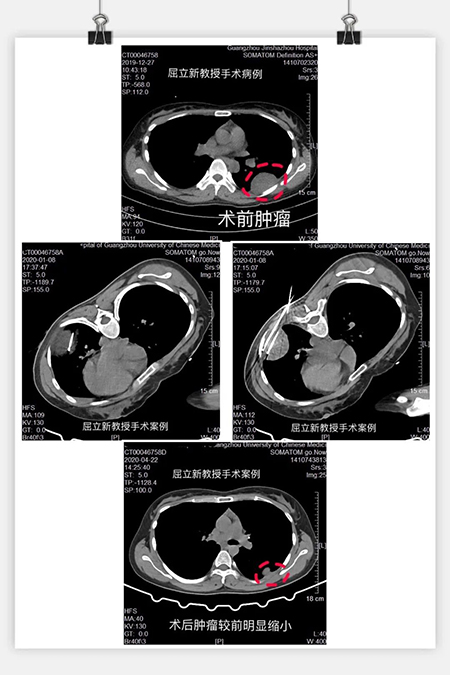

患者为女性,2年前发现“右耻骨肿瘤”于中山大学第一附属医院行“右侧耻骨、坐骨间叶源性恶性肿瘤”切除术,后进行了放疗30次化疗12次治疗。但2019年底肿瘤又转移到了鼻咽部,又行了“鼻部肿物切除术”,术后病理证实为横纹肌肉瘤,住院期间复查胸部增强CT提示双肺多发转移瘤,部分病灶累及胸膜。2020年转诊我科求医屈教授,给她进行了左肺转移肿瘤氩氦刀冷冻消融术,随后又行“动脉造影+灌注+栓塞术”,结合PD1免疫治疗,肿瘤较前明显缩小,疗效显著。